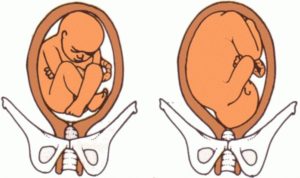

Тазовое предлежание приходится на 20% всех беременностей. При патологии вместо головы к выходу матки располагаются ягодицы плода. На фото хорошо видно, что при ягодичном предлежании головка ребенка упирается в верхнее дно матки.

Плод в тазовом предлежании располагается в матке головой вверх. Получается, что таз ребенка находится снизу, а это нестандартно для естественного родоразрешения.

Ребенок в полости матки может иметь следующее расположение:

- Ножное – бедра, одно или оба, разогнуты, а одна ножка располагается у выхода из матки. Такое расположение встречается у беременных женщин в 10 – 30% случаев.

- Ягодичное – ноги ребенка согнуты в тазобедренных суставах и прижаты к животику. Такое предлежание наблюдается у 50 – 70% женщин.

- Смешанное (ягодично-ножное) – бедра и колени согнуты. Встречается подобное положение в 5 – 10% случаев.

95-97% всех новорожденных детей занимают правильное положение в матке головкой вниз – головное предлежание. Возможны также отклонения от нормы. Так, тазовое предлежание плода – это положение плода, когда в тазовое дно входит не головка ребенка, а ножки или ягодицы (представлено ниже в картинках). Различают несколько видов:

- в тазовое кольцо входят ягодицы, ножки при этом прямые, вытянуты вдоль тела, – ягодичное предлежание;

- когда ножки согнуты, прижаты к груди говорят о смешанном ягодичном предлежании, поскольку ягодицы и ножки ребенка входят в тазовое кольцо;

- возможно также полное предлежание ступнями ребенка, при этом ножки слегка разогнуты;

- иногда одна ножка может быть выпрямлена, а вторая находится в тазовом кольце – при этом говорят о смешанном ножном предлежании.

Вариант расположения плода в матке